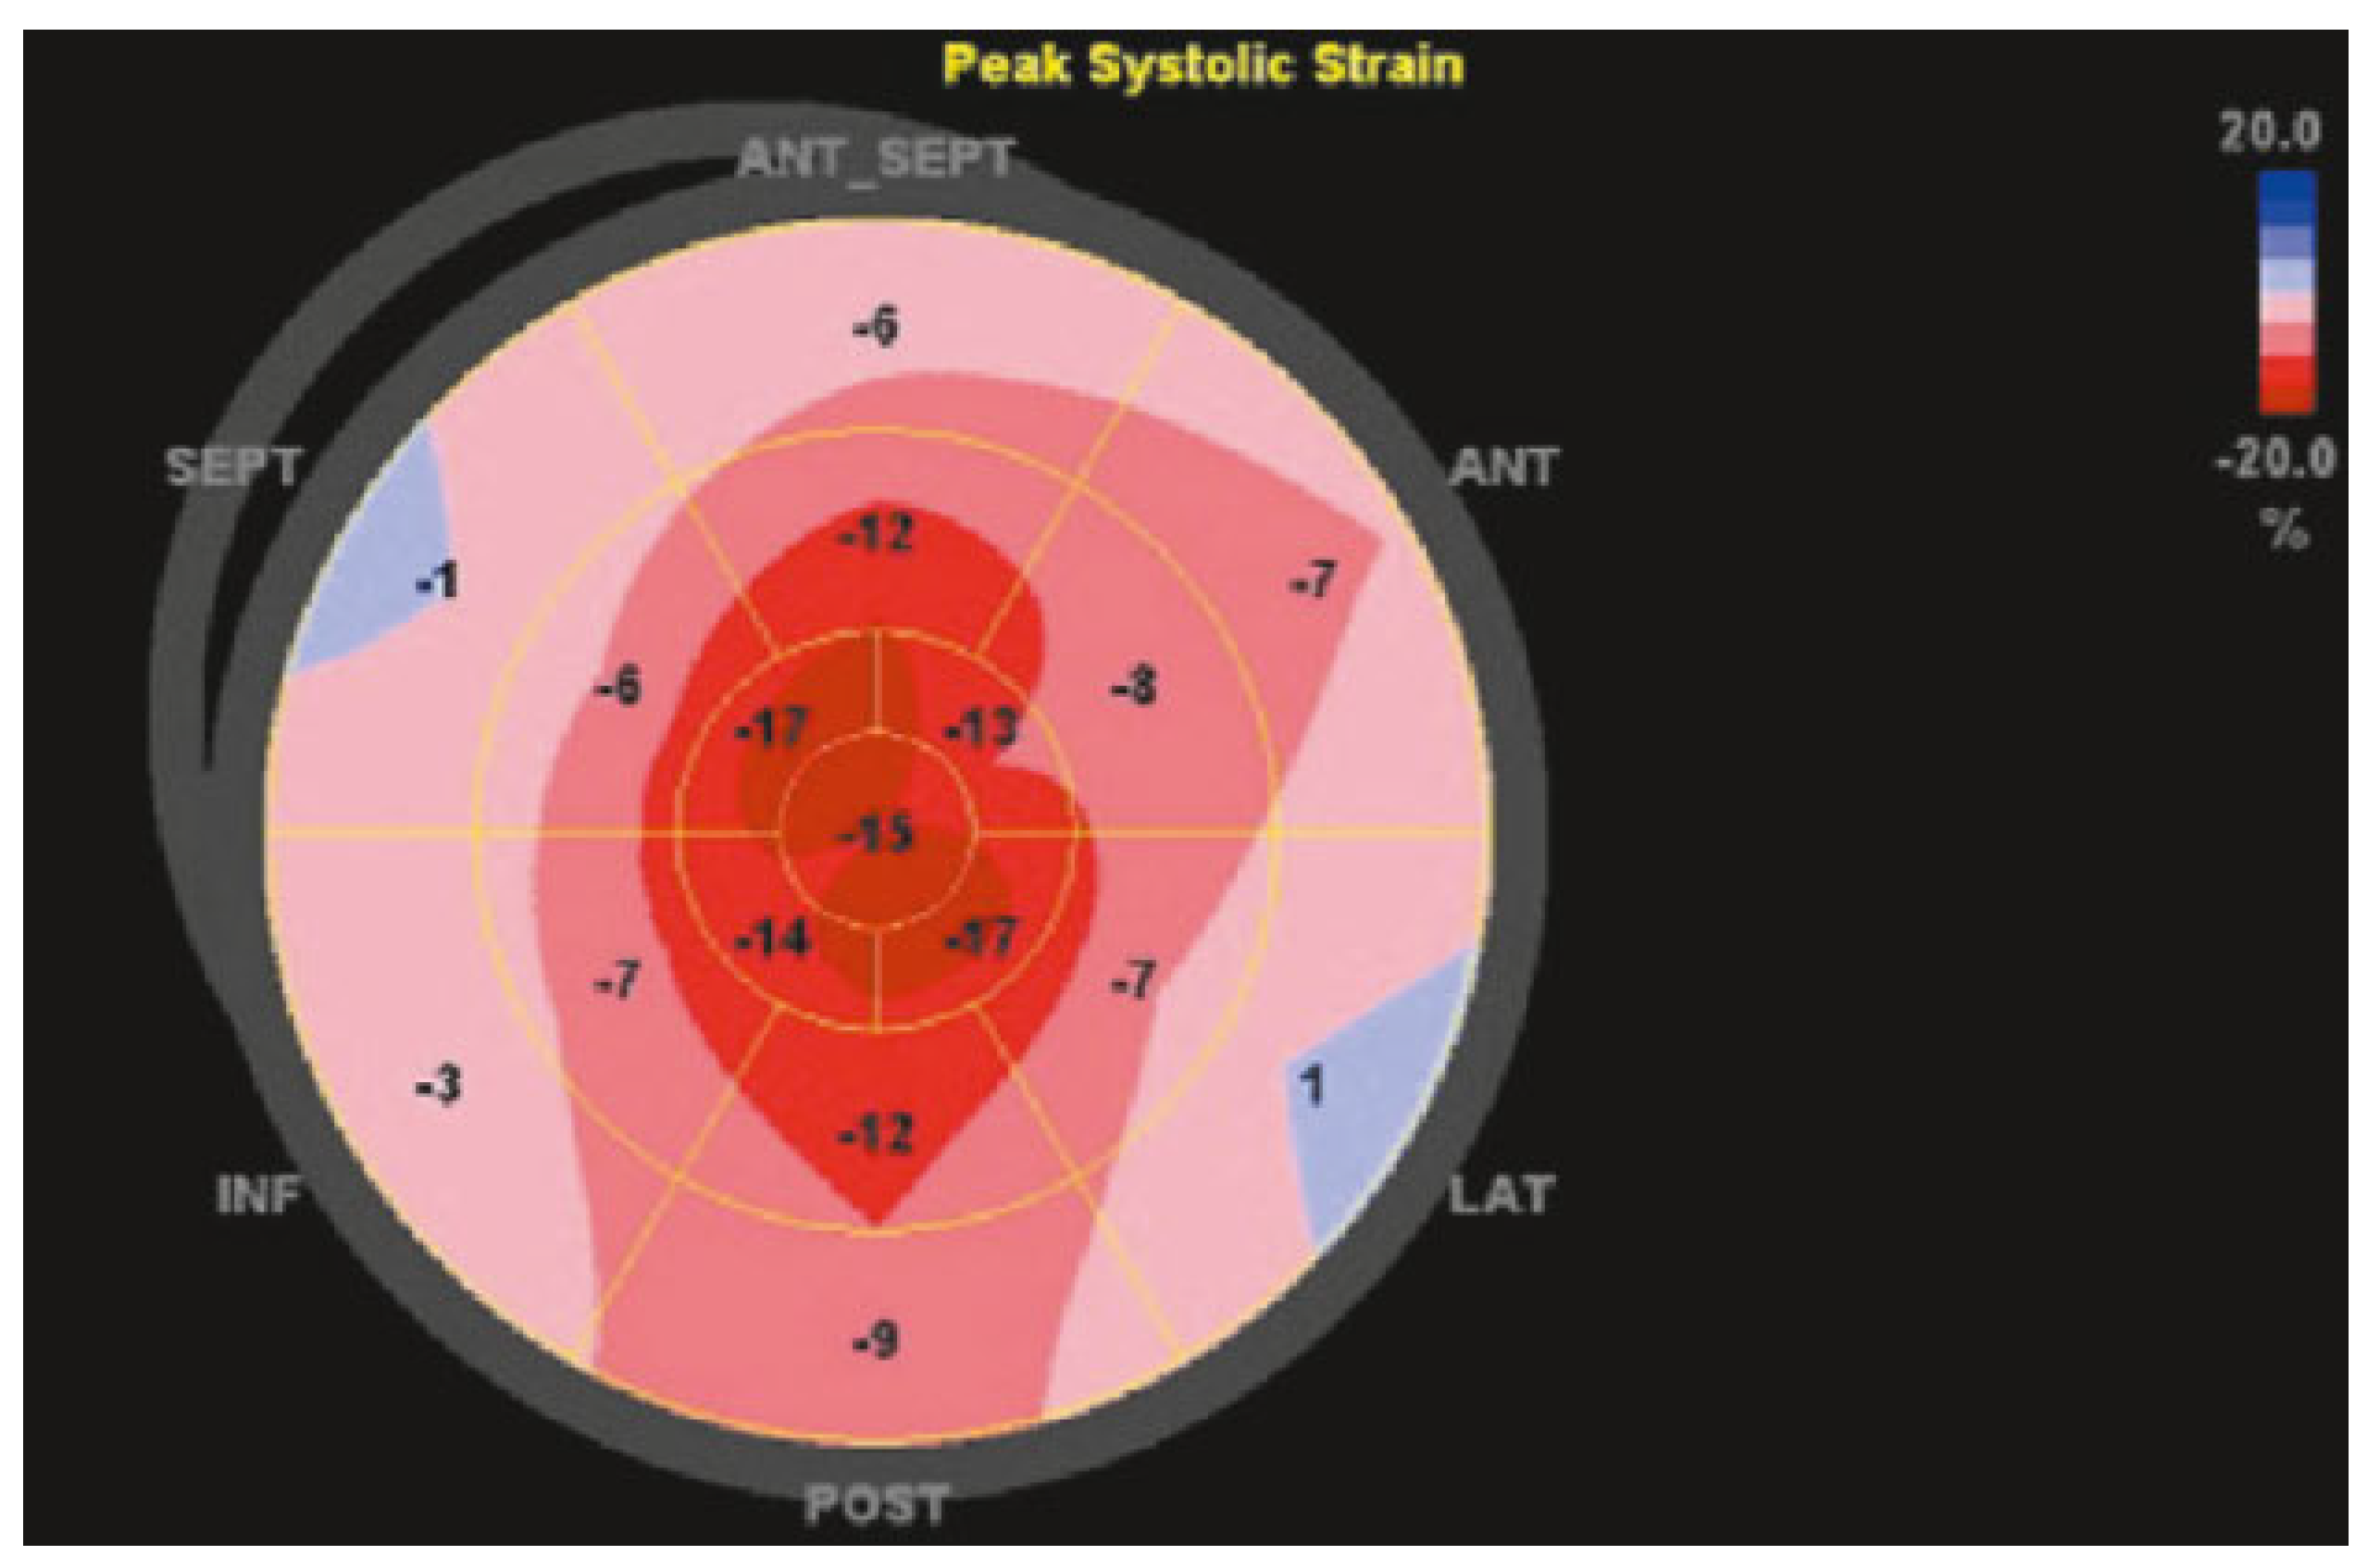

LVEF is certainly important for the assessment of systolic function in patients with cardiomyopathies. Additional diagnostic and prognostic value is offered by the use of strain analysis. In the early stages of hypertrophic cardiomyopathy, global longitudinal systolic strain is reduced, although radial and circumferential strain may be well preserved, maintaining LVEF within a normal range. This pattern may also point towards a higher degree diastolic dysfunction [

23]. In addition, infiltrative cardiomyopathies such as cardiac amyloidosis ohen present with a typical pattern of preserved longitudinal systolic strain in the apical, but not the basal, leh ventricular segments, resulting in a so-called apical sparing pattern and providing potentially useful incremental diagnostic information (

Figure 1).